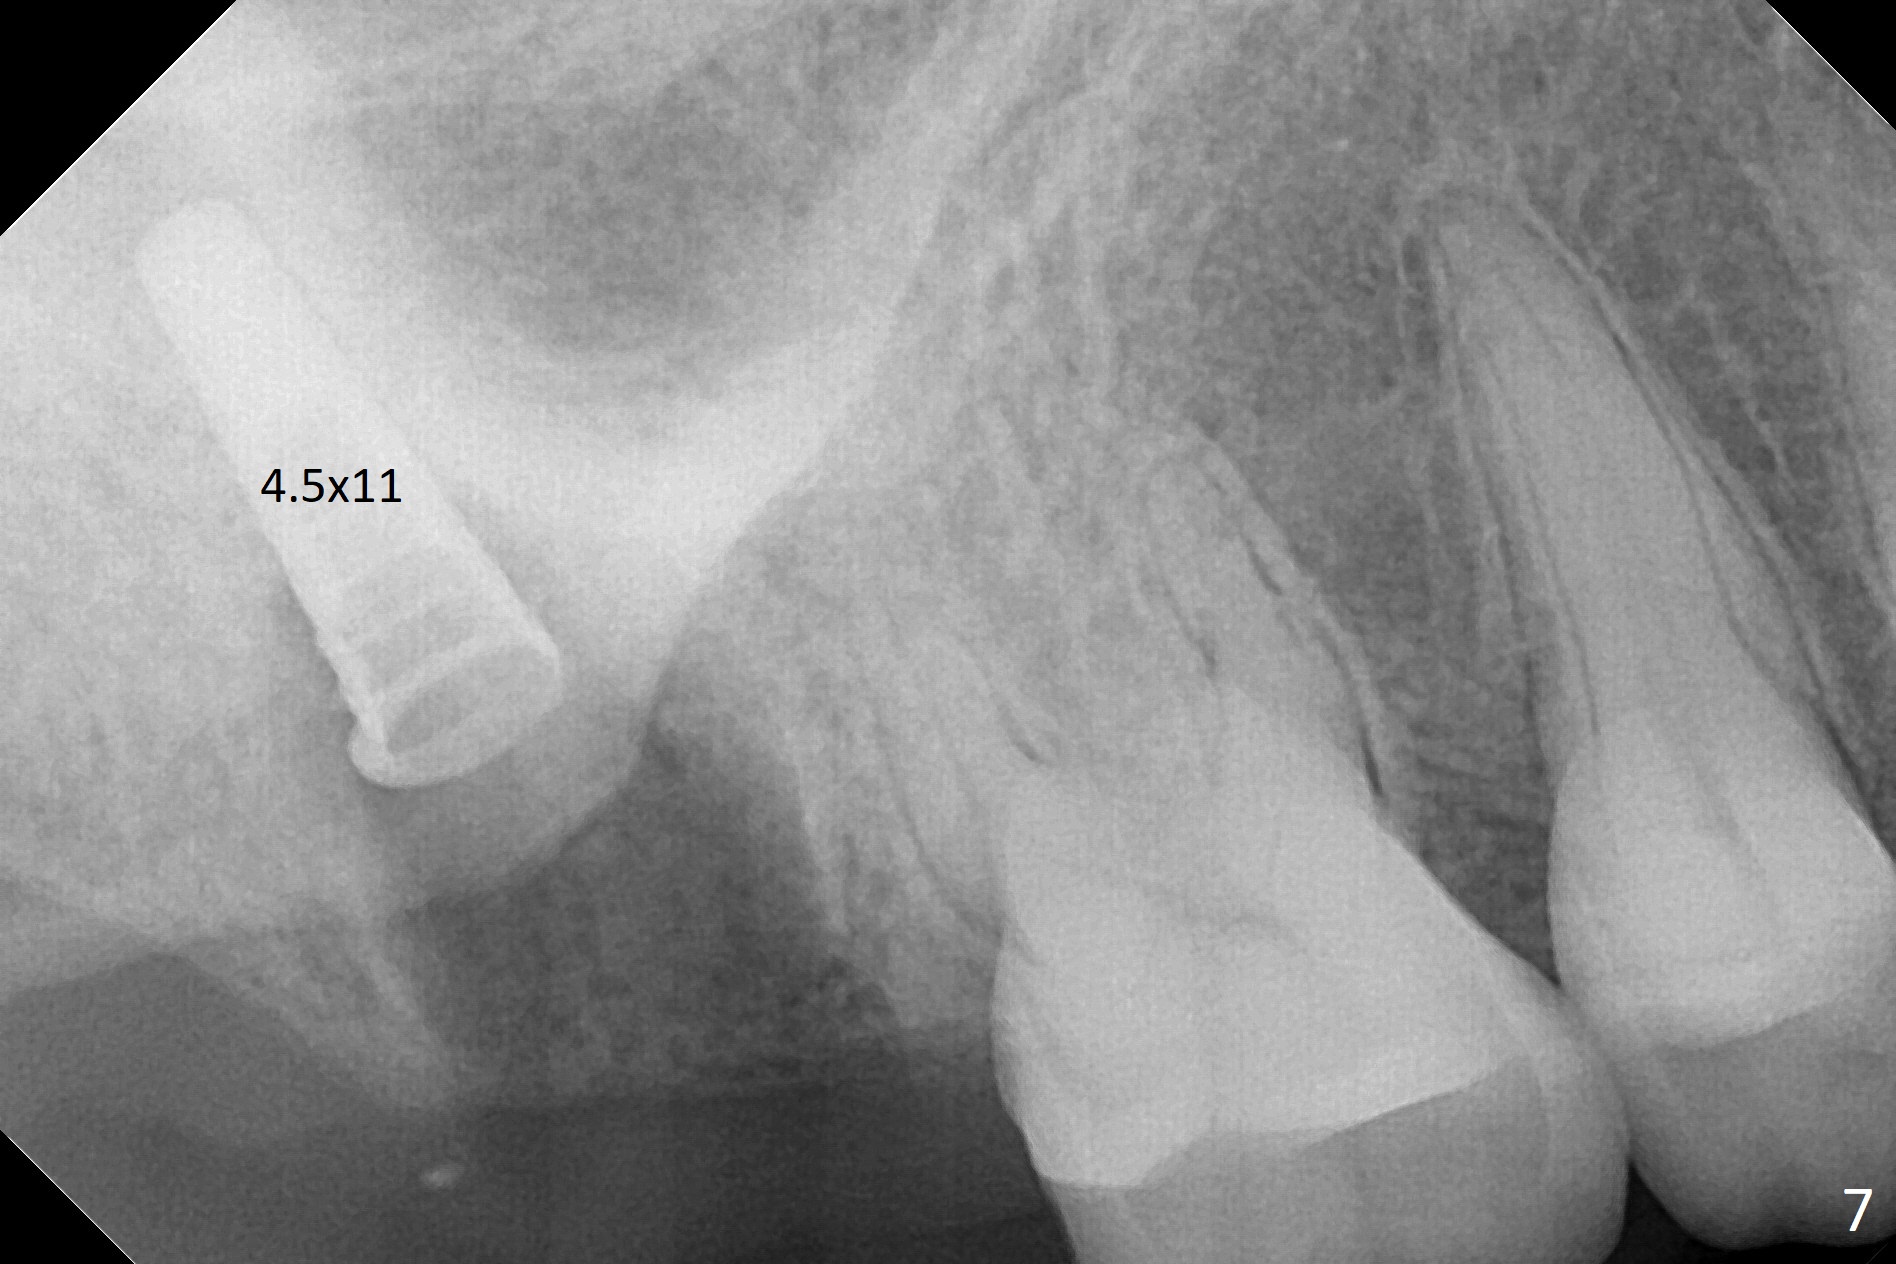

Fig.5 shows the mesial slope of the socket (M), which is more or less the center of the socket mesiodistally. If the osteotomy were set up in the red circle (Fig.6) in the mesial slope (Fig.8 green dashed line), the trajectory of 4.5x11 mm dummy implant (Fig.7) would be more ideal (Fig.8 red outline) with more native bone contact. Finally a longer IBS implant is placed (4.5x15 mm, Fig.9,10) to achieve primary stability (50 Ncm). When the provisional is removed for impression 3 months 10 days postop, the implant is found to have been placed distopalatally (Fig.13), which should have been avoided. It appears essential to use guide for a distal implant. It is agonizing to re-encounter the off-axial implant (Fig.14) and the distopalatal access hole (Fig.15) 1 year post cementation. It is also amazing that the abutment screw has not loosened. A fair-sized piece of bone graft has just been removed buccally (Fig.15,16). The patient complains of sensitivity 2 years 3 months post cementation, although there is no abnormality around the implant crown. Guided surgery is essential to avoid restoration complication. There is no thread exposure nearly 3 years post cementation; in fact the apical portion of the abutment is covered by the bone (Fig.17,18).